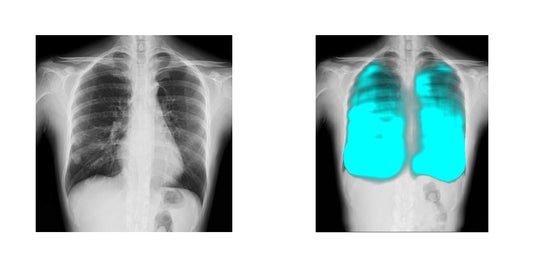

コニカミノルタのX線動態解析技術/イメージングAI技術と、FPTの高度なAI技術を活用し、呼吸器疾患の診断支援、医療レポートの自動生成など新しい診断技術の確立を目指します。コニカミノルタ独自のX線動態解析は、世界で300件以上の特許を取得しており、既に400台以上の販売実績があります。ベトナムの医療イノベーションとデジタル変革による呼吸器疾患対策を推進することで、国民の健康と医療従事者の負担軽減に貢献します。

- 簡易かつ高度なX線動態解析画像を用いた呼吸器疾患に関する医療指標の開発と、AI診断支援ツールの開発による呼吸器疾患の早期診断機会創出

コニカミノルタはデジタルX線動態撮影および動態解析を、新しい”動きの診断”を提供するソリューションとして展開しています。この当社独自の技術「X線動態解析」を搭載したシステムとして、一般X線撮影装置を用いて動画を撮影できるデジタルX線動態撮影システムを開発・提供しており、既に国内外の医療機関で導入実績があります。